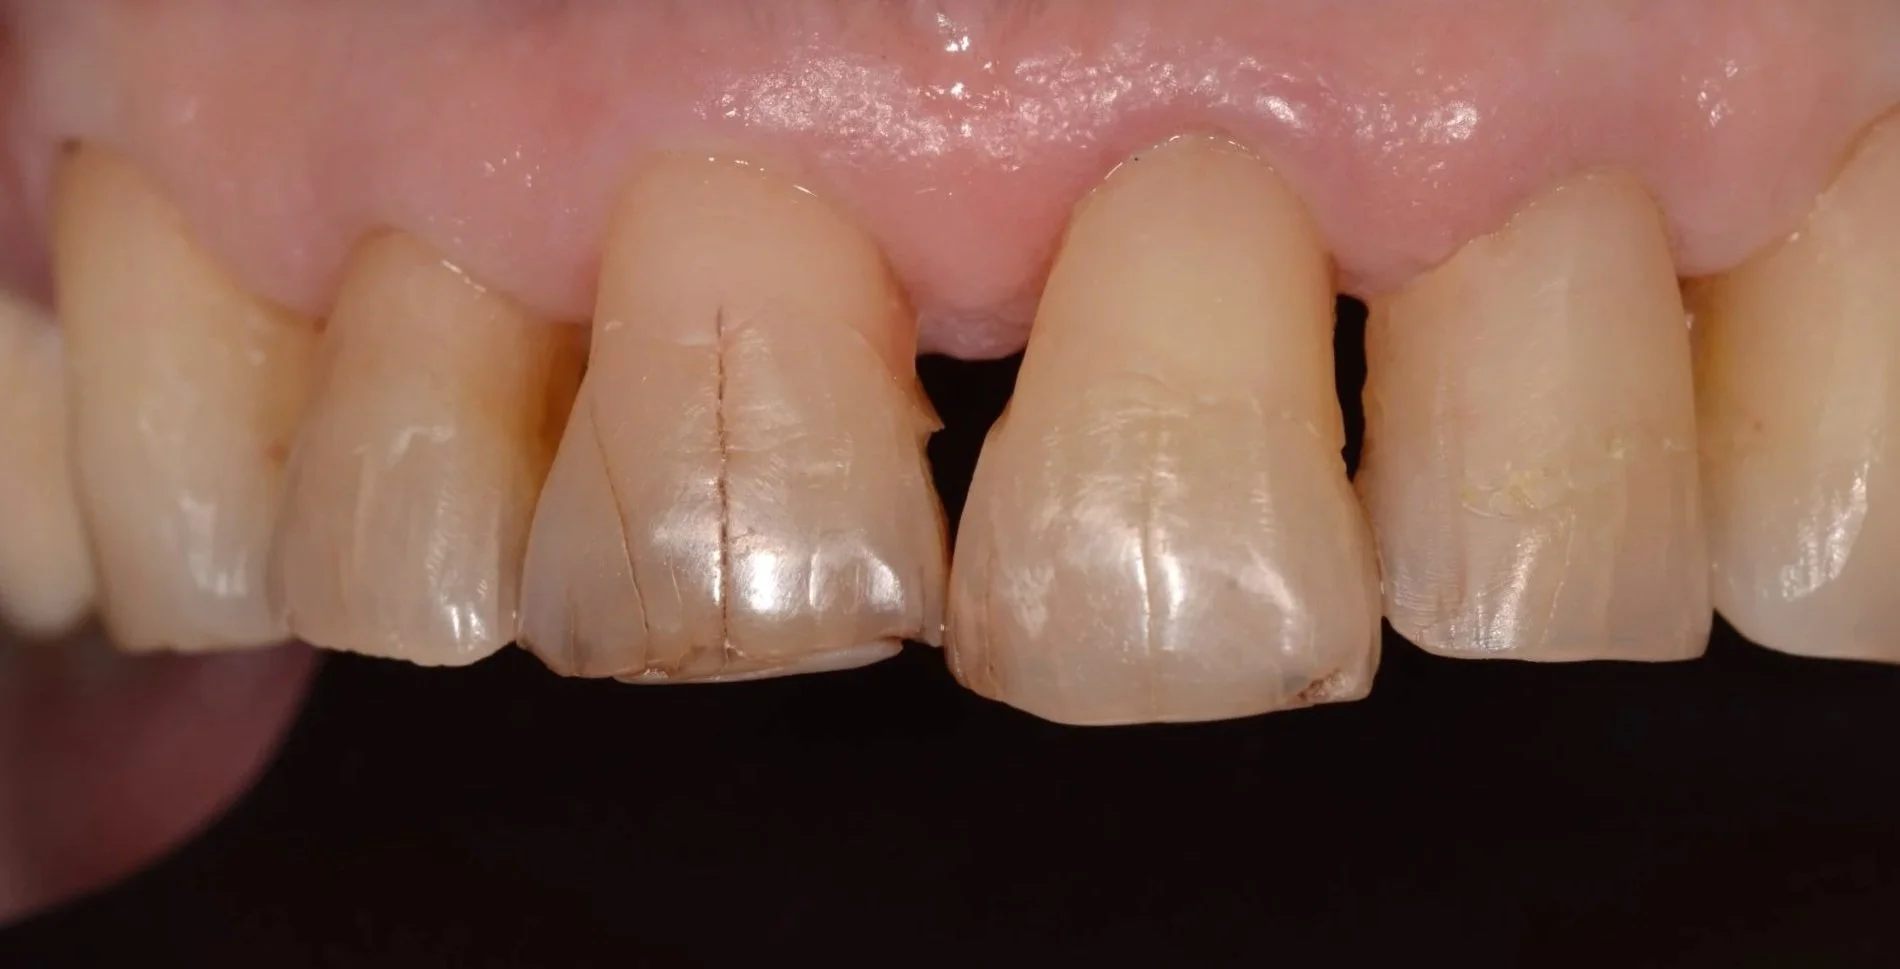

Eliminación de caries y restauraciones

Tallados